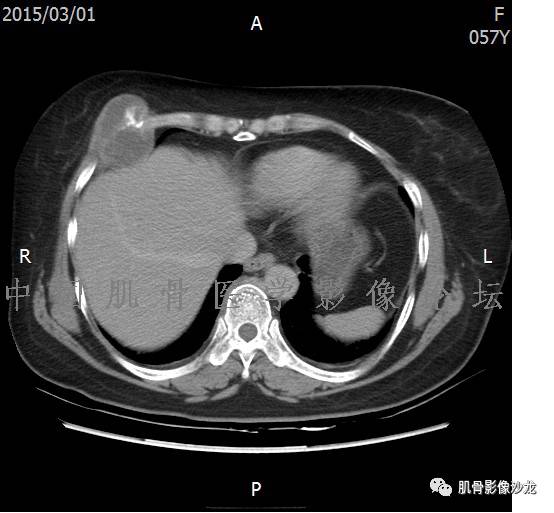

患者2月前无明显诱因下感右腿疼痛、麻木,疼痛呈持续性,发作时无法行走,休息后可缓解。当时无明显肿块,患者遂至当地医院就诊,查X片见右髂骨骨质破坏。6周前患者自觉右髋部渐大肿块,初肿块较小,后肿块逐渐增大,现肿块约12*10cm大小,有压痛。患者遂至我院就诊,查MRI:右髂骨异常信号,伴软组织肿块。ECT、肺CT未见转移。现患者为求进一步治疗,门诊拟“右髂骨肿块 ”收治入院。 患者发病来,神清,精神可,胃纳夜眠可,二便无殊,体重无明显变化。

1、软骨肉瘤可以有膨胀性骨质破坏(病例3,4),可以有溶骨性骨质破坏(病例2),局部皮质因为破坏变薄,中断 ;

2、软骨基质T2WI高信号,软骨小叶分叶状,也就会出现高老师提到的骨内膜扇贝形压迹。一般认为骨内膜扇贝形压迹超过骨皮质厚度的2/3是软骨肉瘤在长管状骨的特征性表现。如上图。3、软组织肿块或肿胀;

2、软骨肉瘤的发病部位排名:最好发部位为髂骨,其次股骨、肱骨和脊柱。